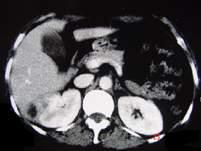

问题 女,12岁,右腰部疼痛10天,尿检可见大量的脓细胞CT平扫+增强如图所示,应诊断为 ( )

选项 A、右侧肾癌 B、右肾结核 C、右侧感染性肾囊肿 D、右肾转移瘤 E、右肾脓肿

答案 E